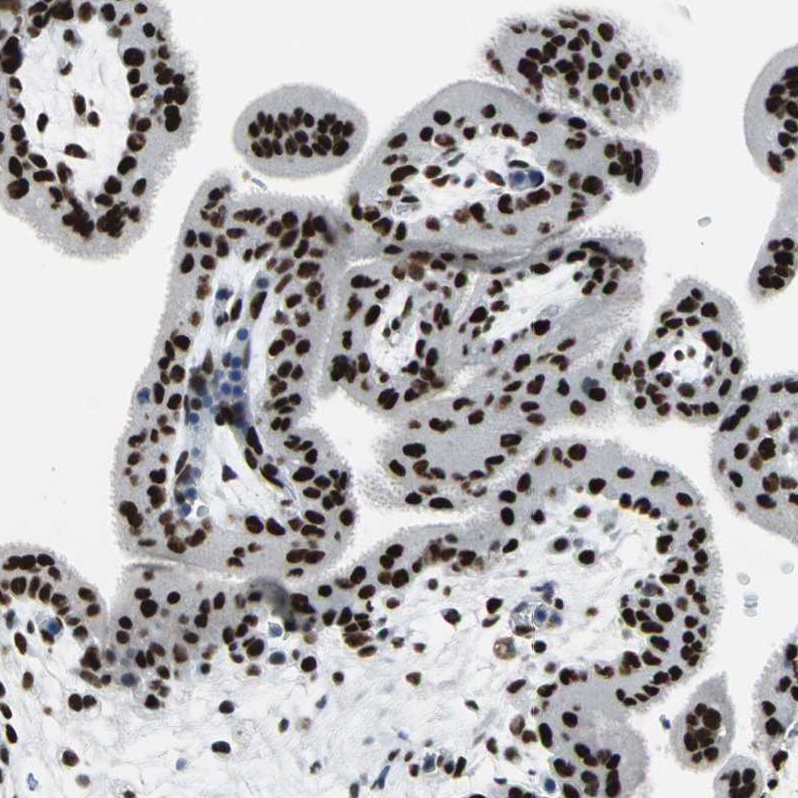

Immunohistochemical staining of human tonsil tissue shows strong nuclear positivity in non-germinal center cells and germinal center cells.